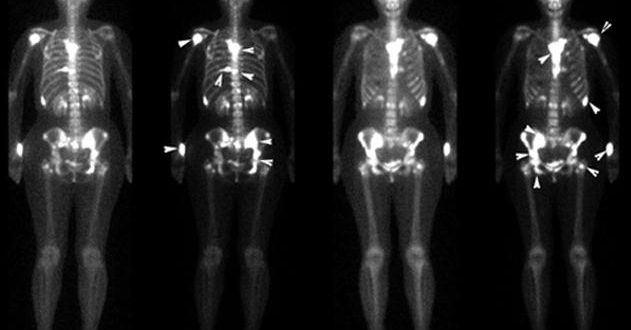

Что такое сцинтиграфия Чтобы понять, что это такое сканирование костей скелета, нужно рассмотреть принцип работы метода. В процессе исследования радиоизотопы, входящие в состав радиофармпрепарата, введенного предварительно в организм…